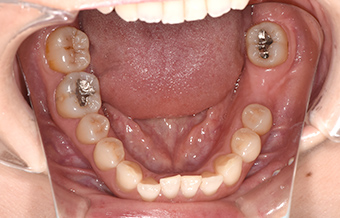

after

| 行ったご提案 ・治療内容 |

抜歯した箇所へのインプラントの埋入をご提案し、患者さまからもご了承いただきました。 |

| 治療期間 | 3か月 |

| おおよその 費用 |

440,000円(税込) <内訳>インプラント体:220,000円、上部構造:165,000円、ガイド装置:55,000円 |

| 術後の経過 ・現在の様子 |

「見た目も良く、自分の歯と同じように噛むことができるようになった」と喜んでおられます。 |